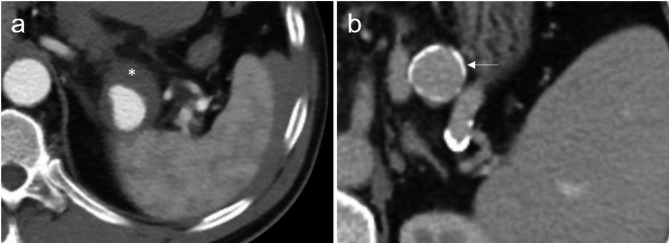

Growth dynamics of splenic artery aneurysms: morphology, comorbidities, and vascular anatomical factors.